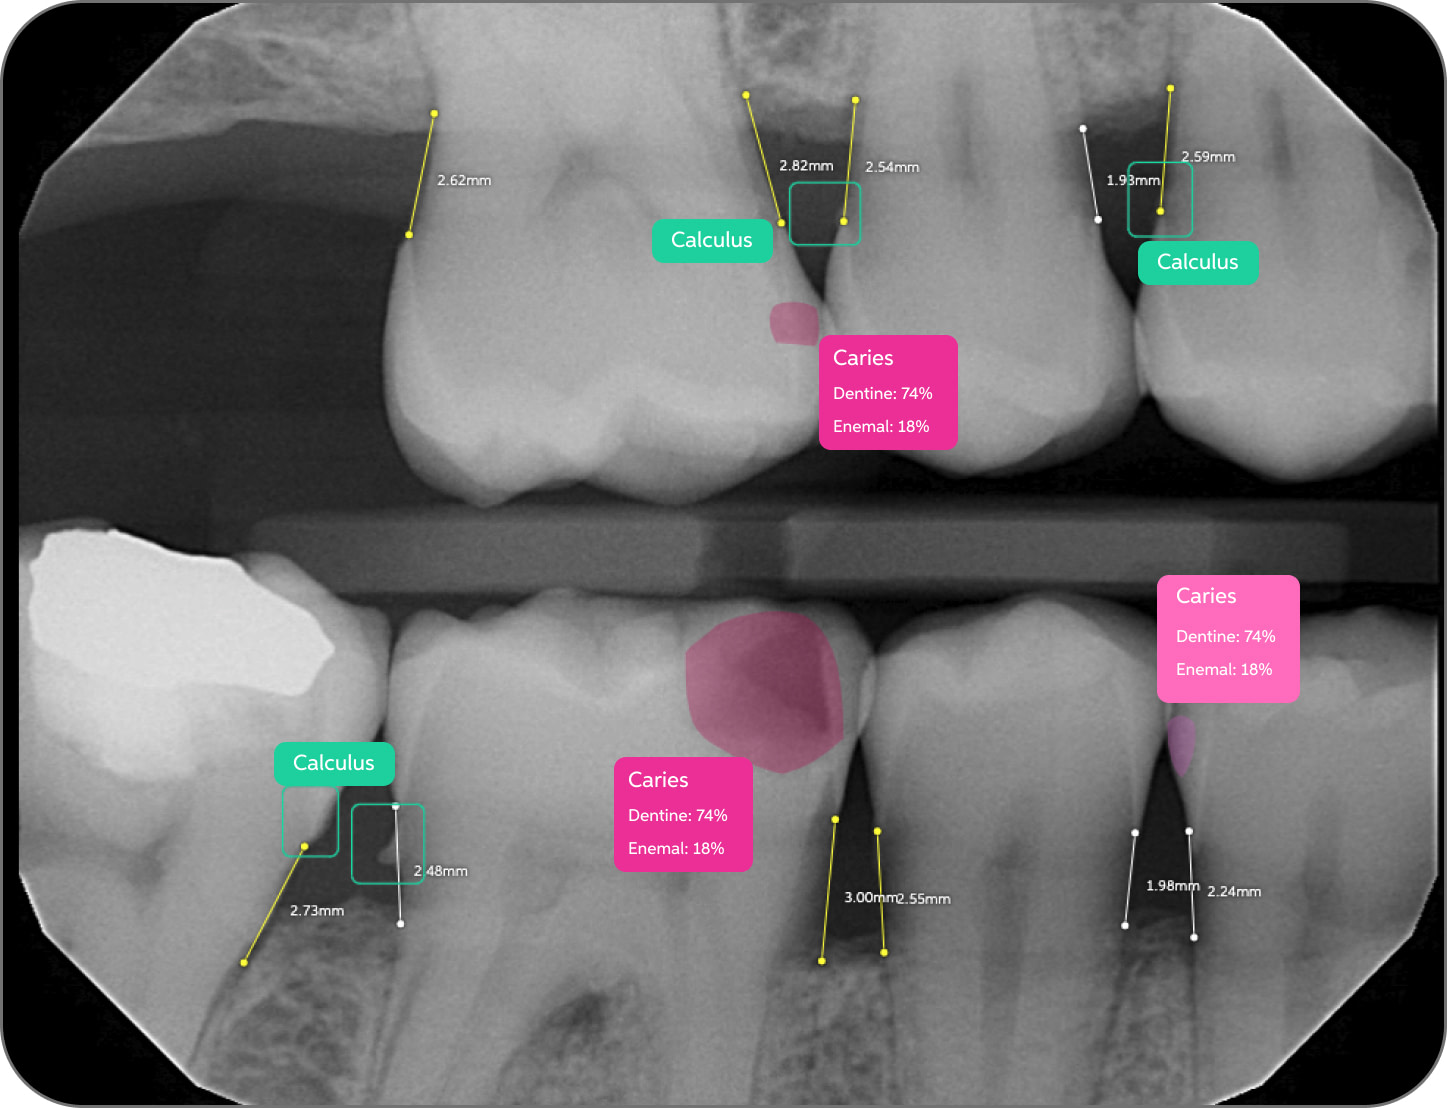

Bone Measurements

The system provides automated measurements from the crest of the bone to the cementoenamel junction (CEJ). These measurements are color-coded to indicate severity:

- White: 0-2.5 mm

- Yellow: 2.5-4 mm

- Amber: >4 mm

This feature is helpful for periodontal assessments, streamlining the process of identifying areas of bone loss. However, it's important to note that image angulation can affect the accuracy of these measurements, a limitation the system acknowledges.

I found these lines to be incredibly useful when describing patients' periodontal health. Cool feature, no doubt.

Calculus Detection

Green squares highlight areas of radiographic calculus. This tool is useful for hygienists and dentists in treatment planning and patient education.

Quite self-explanatory and the system didn't seem to miss often, if ever.

Caries Detection

The best for last and arguably the most well-thought-out feature. Especially with the tooth segmentation mode, which makes it easier for patients to understand their diagnosis and treatment plans.

The system uses two shades of pink to indicate potential caries:

- Light pink: Incipient caries (100% in enamel) - we will often review

- Darker magenta: Caries extending into dentin - we need to restore

The system even provides a percentage breakdown of enamel vs. dentin involvement. I have been blown away by its accuracy while using it, and it makes something that feels quite subjective (reading shades of grey) into a science.

This feature is very useful for patient education and deciding between preventive measures and restorative treatment. However, remember that radiographic evidence alone is not always sufficient for a definitive caries diagnosis.